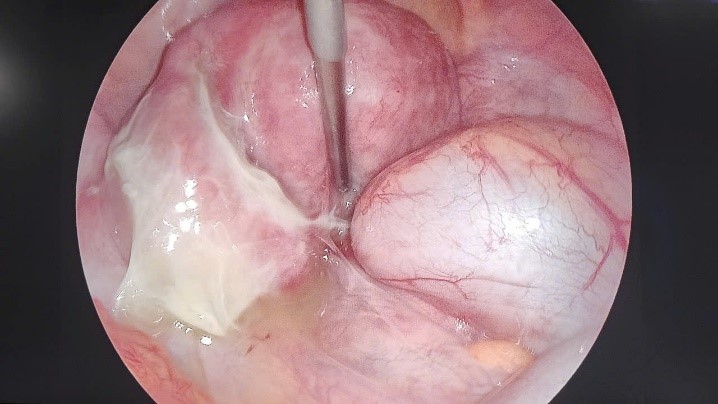

![]() |

Hình ảnh trước và sau phẫu thuật điều trị áp xe phần phụ